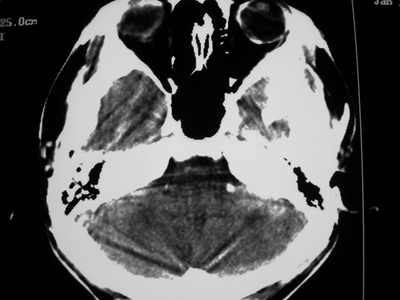

以下是引用卜一在2007-1-19 15:29:00的发言:[br]治疗前:1月14日右侧额叶皮质下低密度影,而治疗后:1月18日右侧阴影消失,新近出现左侧额叶侧脑室前角旁大片状低密度影,边缘模糊。支持—双侧额叶后部缺血性脑梗塞。